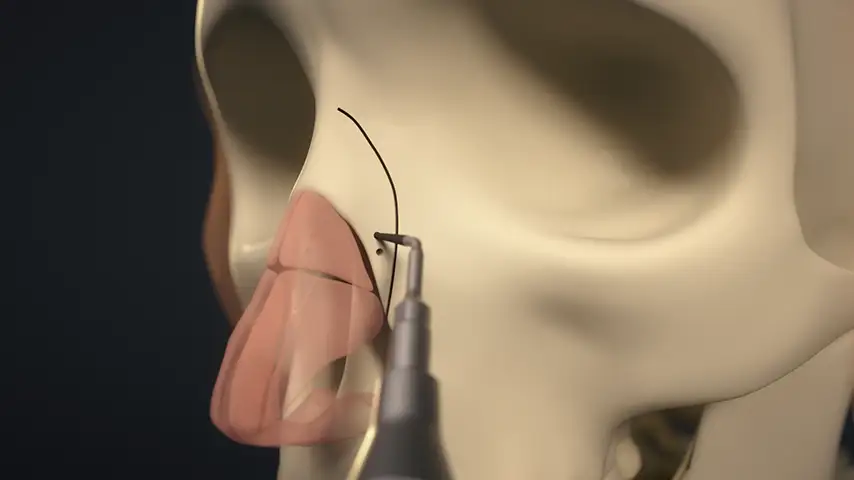

Lateral osteotomy of nasal bone

Transverse osteotomy of nasal bone

Drilling of septum for suture fixation

Details

The finest and angled insert for insertion in limited space;

ideal for perforating nasal bones as well as ethmoid lamina splints.

Recommended insert: